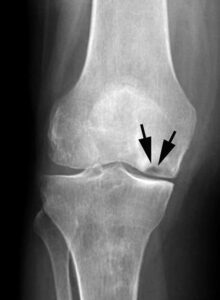

X-ray shows osteonecrosis at the lower end of the femur (thighbone) in the medial femoral condyle.As osteonecrosis progresses, narrowing of the joint space can occur due to loss of articular cartilage.

This MRI scan shows osteonecrosis in the medial femoral condyle. An MRI is often used to detect early symptoms of the disease.